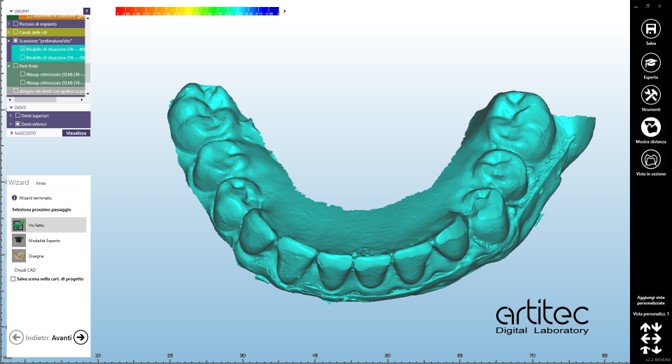

foto 07 scansione inferiore con ribasatura

foto 09 scan body superiore

La fase protesica inizia con la ribasatura delle protesi provvisorie per rilevare la corretta anatomia della cresta. Quindi si procede a scansionare con scansione intraorale le impronte ottenute fuori dal cavo orale, poi le protesi provvisorie ribasate ricollocate nel cavo orale e la loro occlusione. Infine, si scansionano le creste edentule dopo aver posizionato gli scan body per tecnica digitale per rilevare la posizione degli impianti. Per la pianificazione sono scattate delle fotografie intraorali ed extraorali per la definizione dei limiti perimetrali del volto al fine di poter eseguire la programmazione del caso tramite il software di previsualizzazione. Le scansioni così ottenute sono poi inviate al laboratorio per la realizzazione di un prototipo delle protesi in prova.